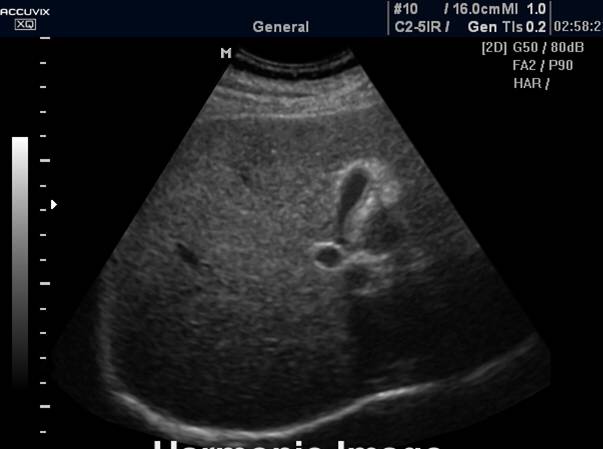

正常肝脏声像图:左图为肝右叶肋间切;右图为肝左叶剑下纵切